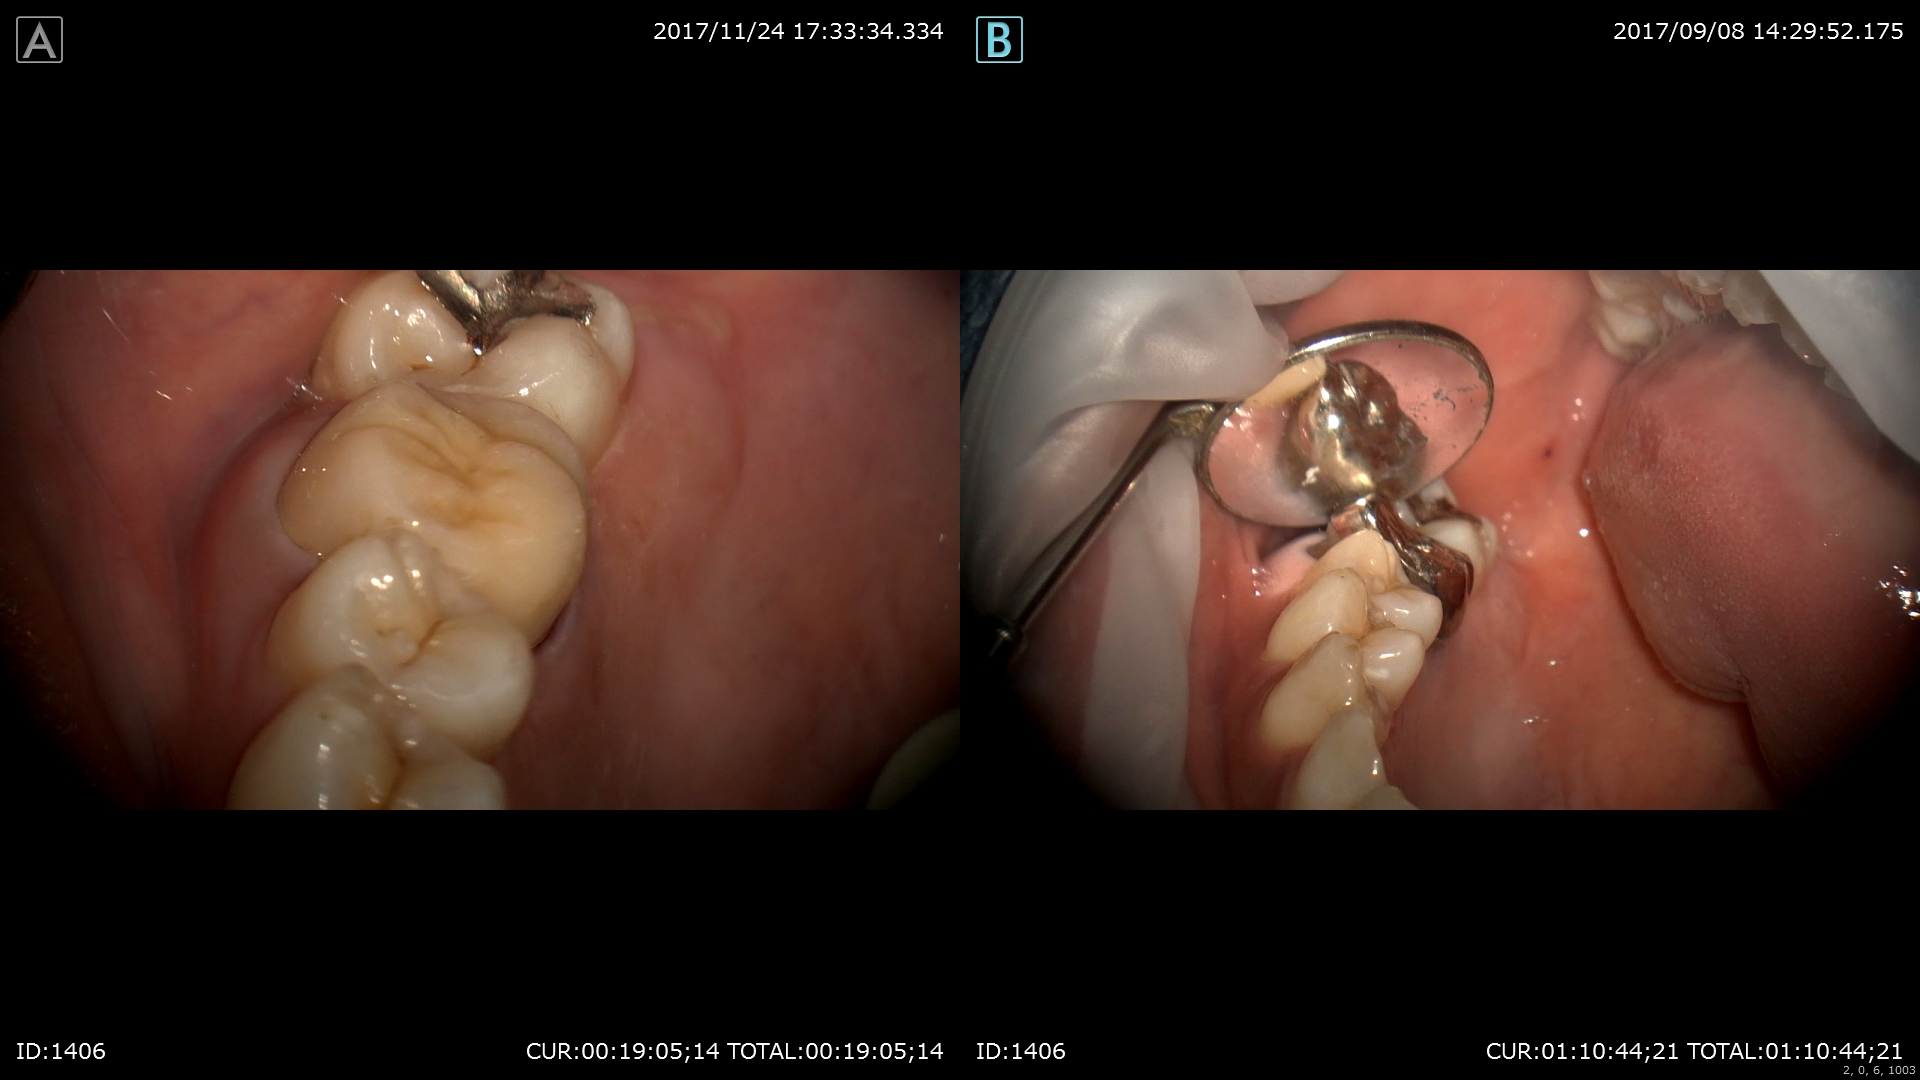

ハイブリットクラウンの装着

仮歯を外して歯肉の炎症がないか見ます。当院では仮歯を入れないでの治療は一切行いません。1つ1つの工程には重要な意味があり歯肉の状態やかみ合わせの関係、細菌侵入のリスクを考え仮歯を入れます。

前回

本日

試適をして

装着

術前右 術後左 金属を使わない治療は体に良いですね。